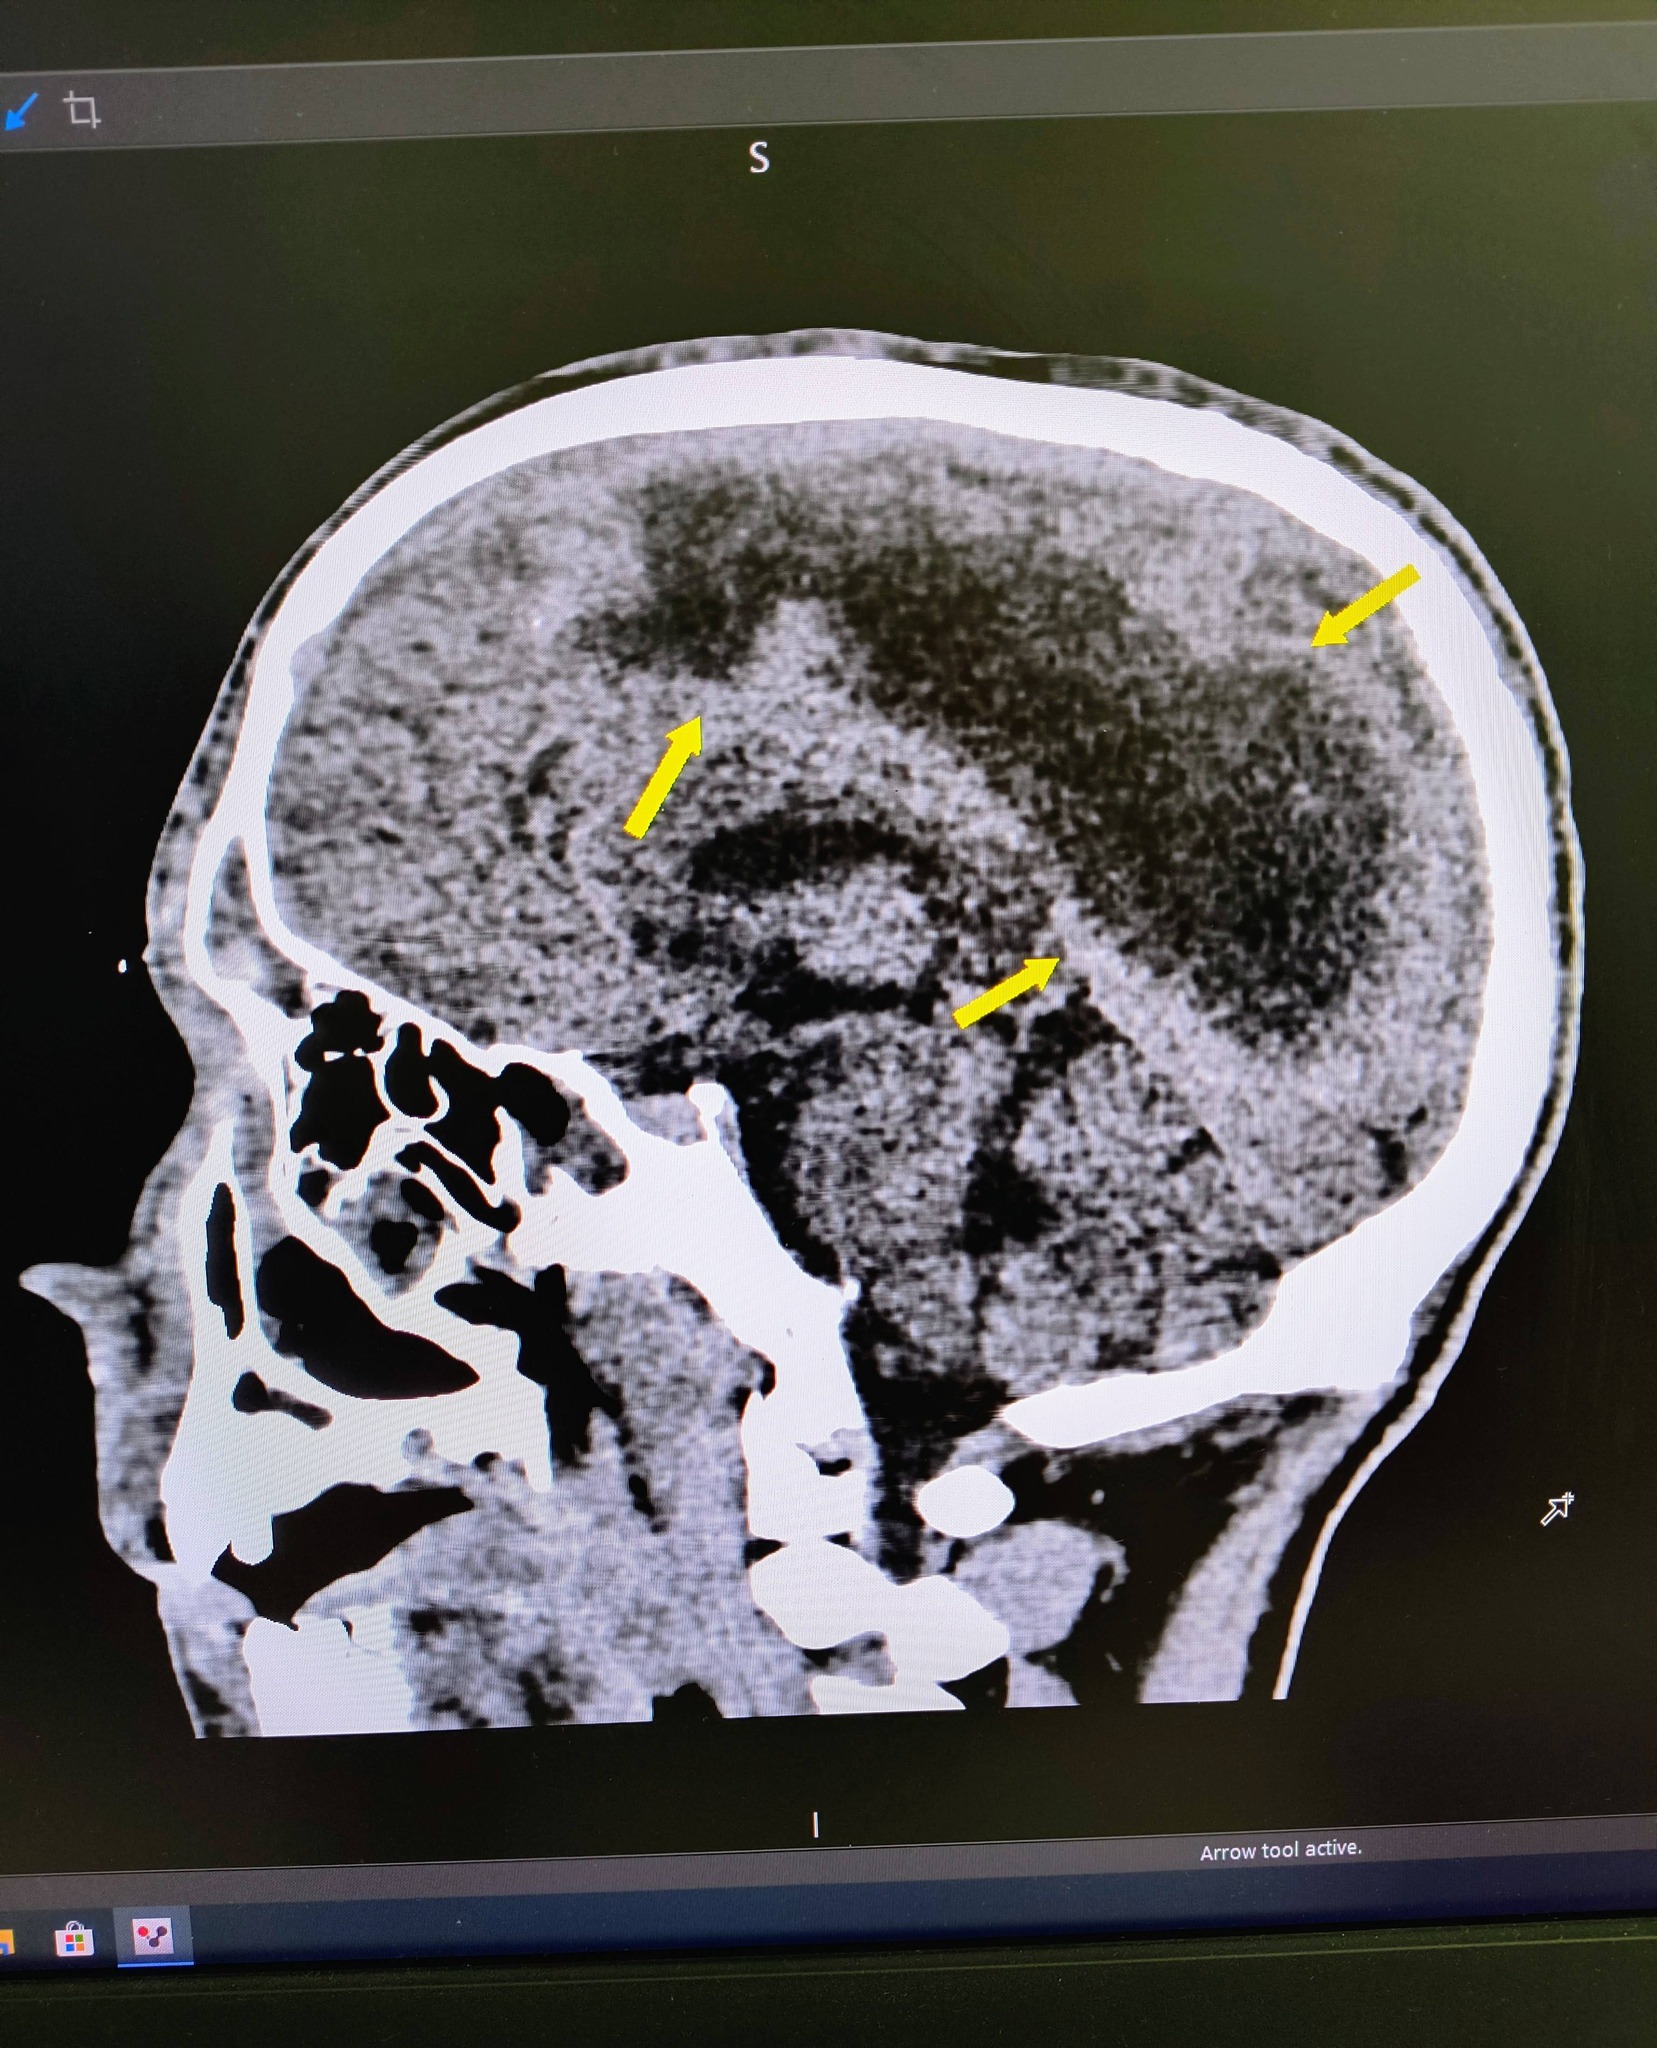

Хлопця госпіталізували у стані глибокої коми. Під час комп’ютерної томографії лікарі виявили емпієму — масивне скупчення гною над правою півкулею головного мозку.

«Пацієнт поступив до нас у стані глибокої коми. За результатами обстежень ми встановили, що причиною є емпієма — критичне скупчення гною в головному мозку. Було негайно проведено оперативне втручання», — розповів нейрохірург Юрій Кузьмінський.